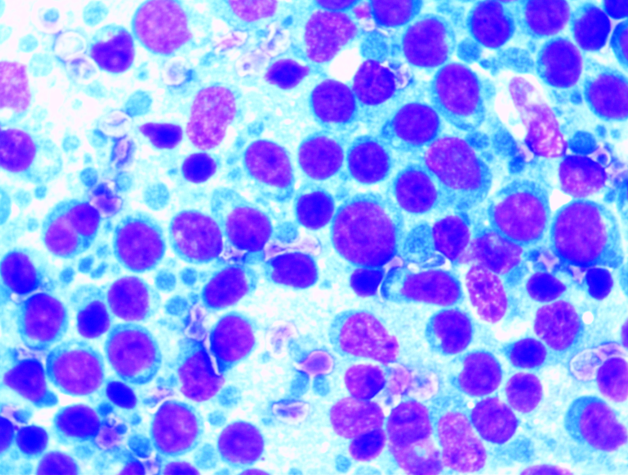

미세침흡인세포검사

미세한 주사바늘로 소량의 세포를 얻은 후 양성 혹은 악성의 세포 진단을 목적으로 시행합니다.

조직검사 이미지

조직검사

병변의 조직을 재취, 재취된 검체를 현미경으로 관찰하여 병변을 진단합니다.